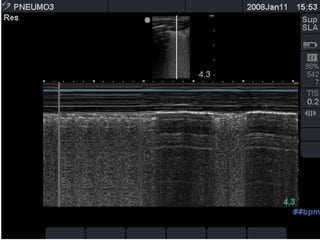

the "seashore sign" (Fig.3).

Absent lung sliding

Exaggerated horizontal artifacts

Loss of comet-tail artifacts

Broadening of the pleural line to a band

The key sonographic signs of

Pneumothorax